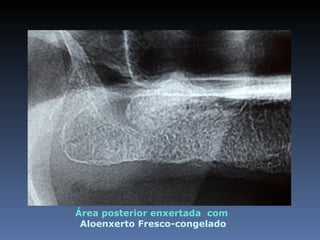

Área posterior enxertada com

Aloenxerto Fresco-congelado